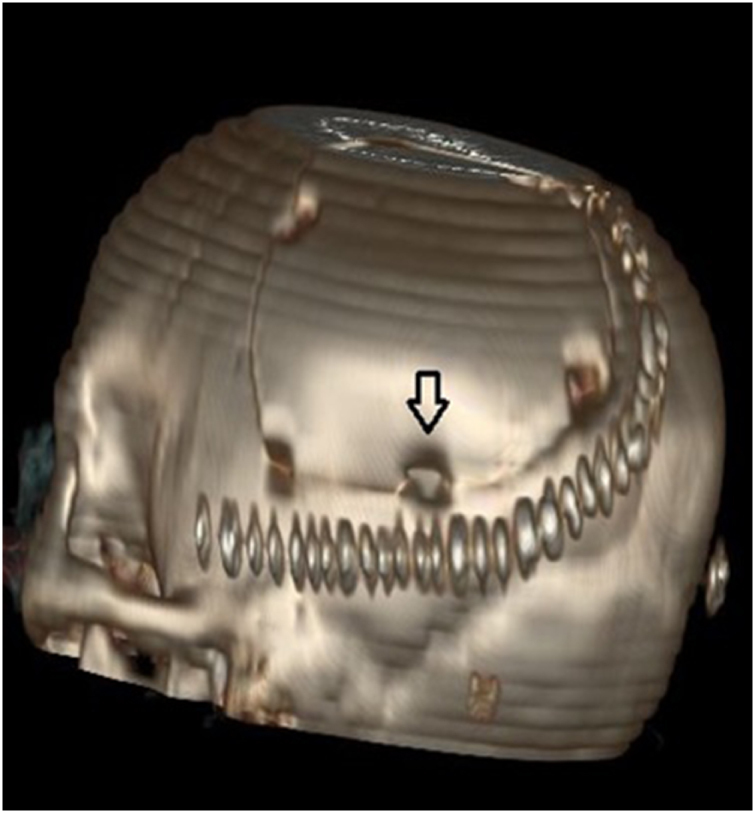

Case presentation: A 14-year-old female presented with headache and seizures. Magnetic Resonance Imaging (MRI) revealed a mass in the trigonal region. She underwent surgical resection of the tumor. On postoperative day 7, she developed a symptomatic cyst at the tumor bed. The cyst was drained, resulting in symptomatic improvement. Follow-up assessments confirmed her clinical recovery.

Conclusion: Minimally invasive percutaneous drainage followed by shunting successfully managed the postoperative cyst and prevented recurrence in this pediatric glioma case. Given the absence of standardized treatment protocols, individualized care is essential to ensure the best possible outcomes.